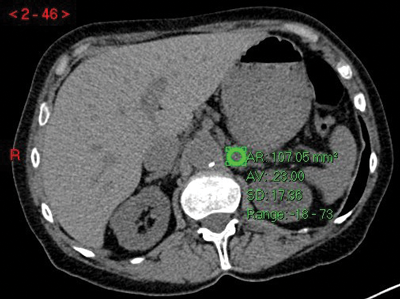

Figure 3:

Top: Unenhanced CT (HU 23).

Centre: Arterial phase CT (HU 74).

Bottom: Delayed phase CT (HU 37).

Absolute washout = (74-37)/(74-23)x100 = 37/51x100 = 72.5% in keeping with adenoma.